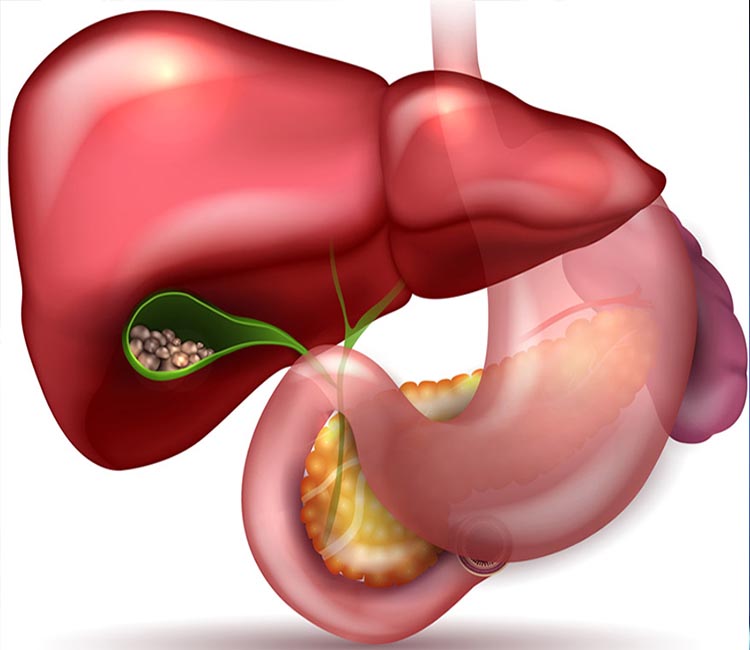

We offer advanced minimally invasive surgery for gallbladder stones, providing effective treatment to alleviate pain and prevent complications, ensuring a quick recovery and long-term relief.